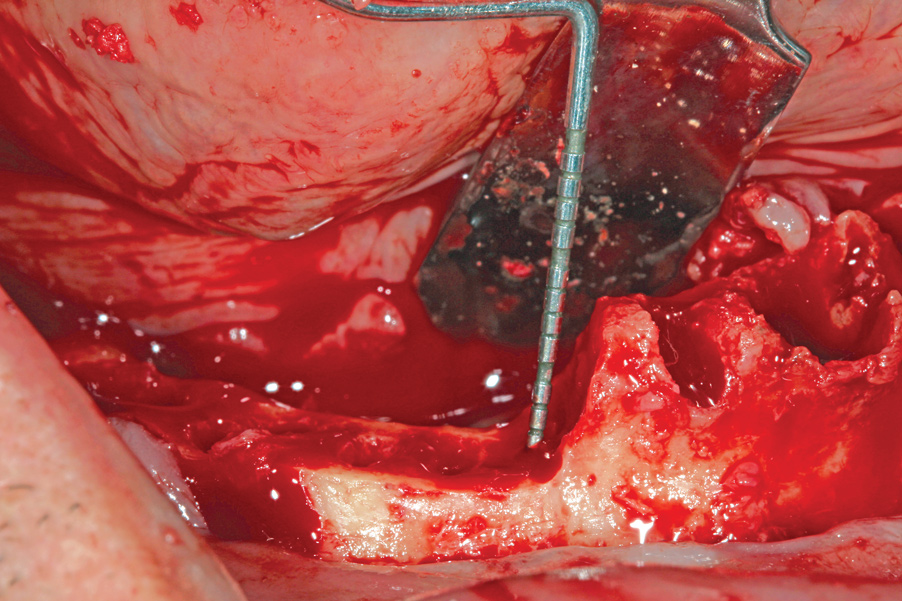

Hemorrhage From Osseous Nutrient Canals

All-on-4–style treatment typically involves reduction of alveolar and/or basal bone (Figure 9) to achieve adequate restorative space for both the interim and final prostheses.25-27 During reduction of this bone, exposure of intraosseous nutrient canals28,29 may lead to hemorrhaging that may obscure visualization of the surgical field. If left uncontrolled, hemorrhaging from nutrient canals can become significant, resulting in excessive blood loss. It is not uncommon to encounter multiple concurrently hemorrhaging intraosseous nutrient canals, especially during mandibular bone reduction.

When faced with this situation, the author uses the blunt end of a handheld instrument, such as a Woodson instrument (Figure 10), to put heavy pressure on bone directly adjacent to the bleeding nutrient canal. This pressure typically deforms the adjacent bone to a point at which it occludes the hemorrhaging. The author has encountered hundreds of hemorrhaging intraosseous nutrient canals and has never had this technique fail to achieve the desired results.

Fig 9. Alveolar bone reduction prior to dental implant placement in a mandibular All-on-4–style dental implant surgery.

Figure 9